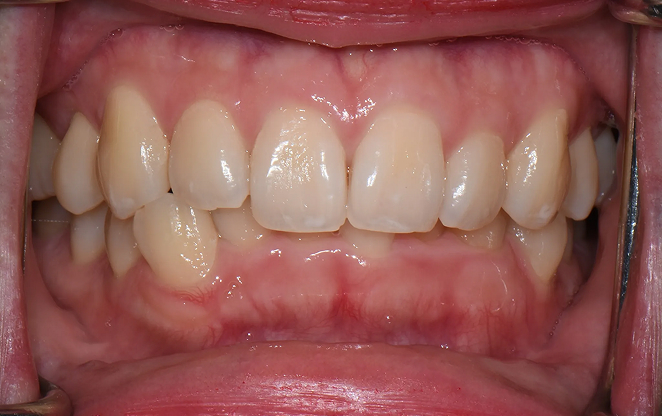

Before

After